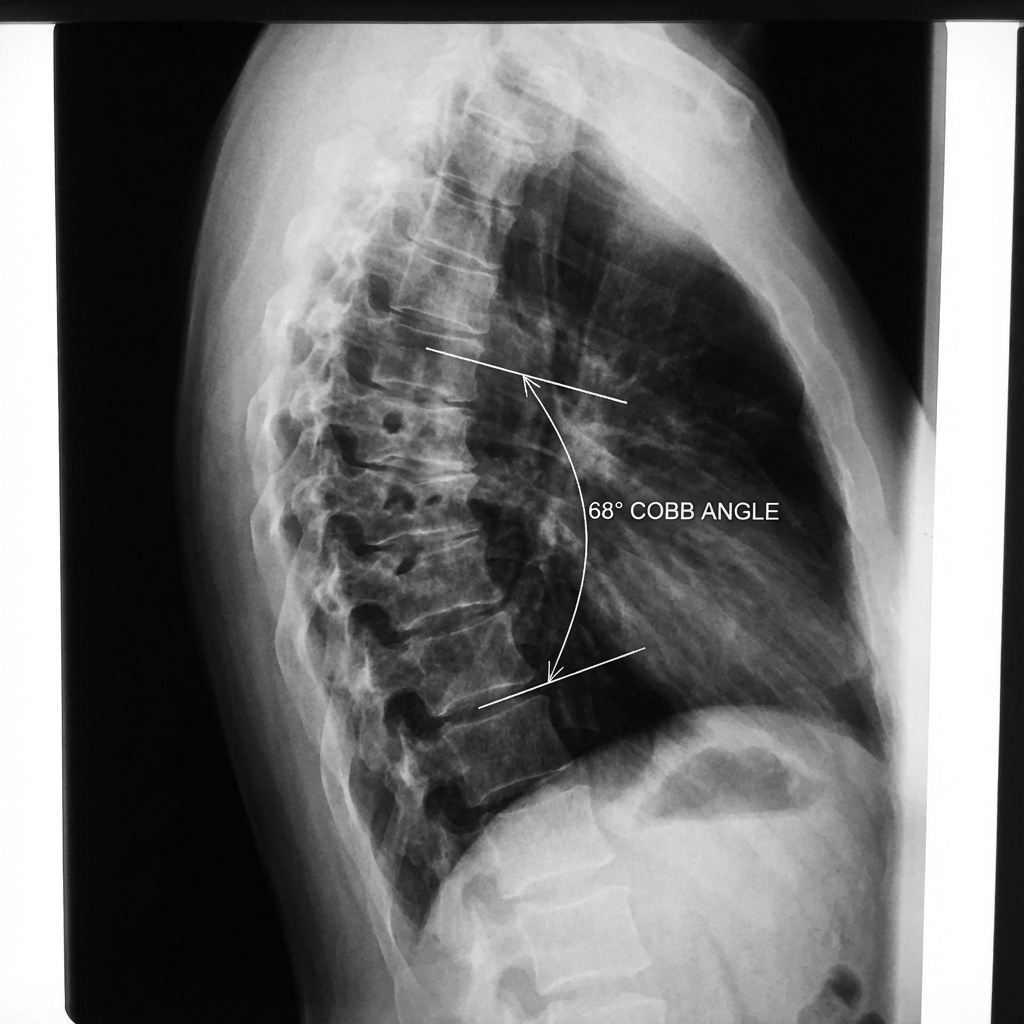

Standing lateral radiograph demonstrating thoracic kyphosis measuring 68 degrees (Cobb T5-T12). There is anterior wedging >5 degrees at T7, T8, and T9 with irregularity of the vertebral endplates and multiple Schmorl's nodes. The apex is at T8. This represents classic Scheuermann's disease with structural thoracic kyphosis.